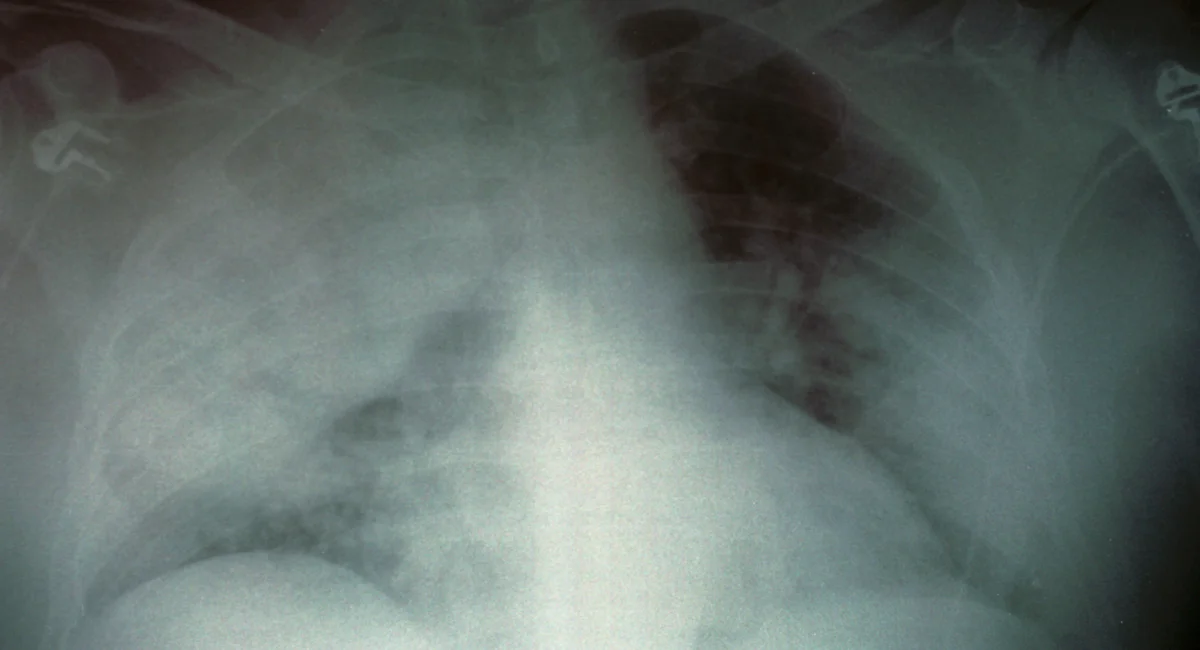

Two cases of Legionnaires' disease have been confirmed at The Christ Hospital in Cincinnati, prompting water testing and safety measures, though the hospital reports no current risk to patients or staff.